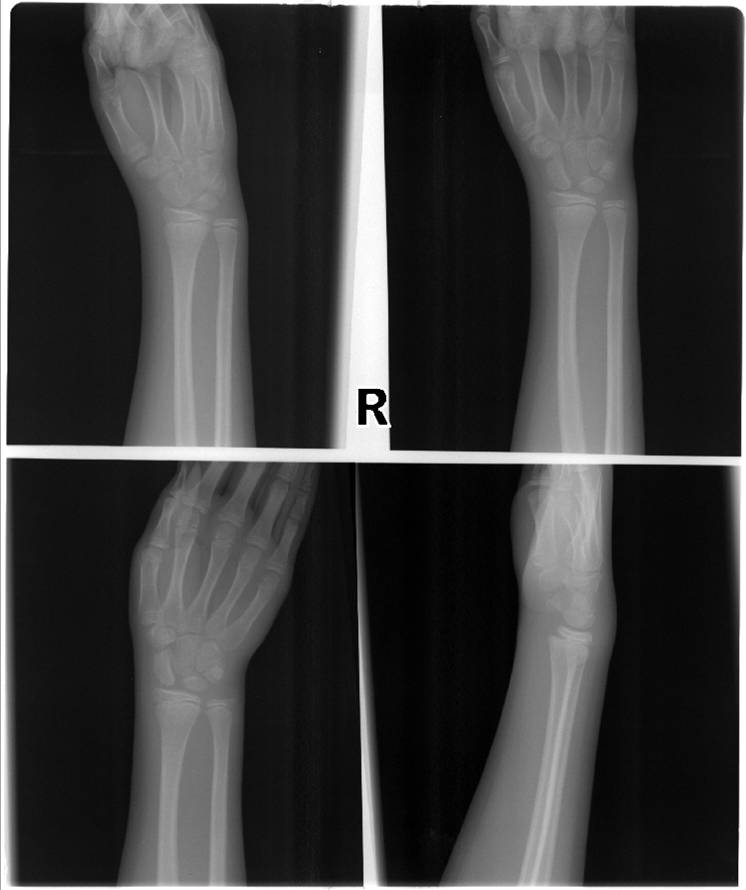

Somewhere in this X-ray it tells the muckity mucks and the brainiac doctors that my daughter has broken her growth plate. Joy. Little Miss Elle was playing on the monkey bars in our backyard when she was hanging upside down, slipped and fell on her wrist and head. I was at first more worried about her having a concussion since her face and lips had no color. It didn't even dawn on me to check her wrist. She finally complained that it hurt and when we took her to Urgent Care they confirmed the break. Joy. So, now we are waiting for a call from the Orthopedic specialist to make a decision on what the next step is. Possibly surgery. Joy.